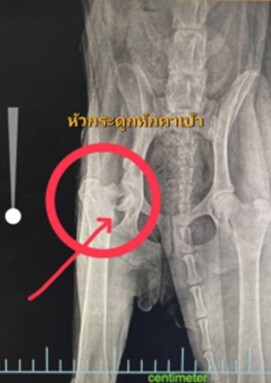

One-year-old Peggy has been enduring agonizing pain in her back leg for an extended period, a distressing situation that initially baffled us and local veterinarians alike. Our vets had no x-ray facilities which meant they were unable to accurately diagnose the underlying issue. A simple x-ray would have told them immediately that Peggy had a fractured femur bone head. Instead they believed she had a straightforward case of joint inflammation which was treated with medication which offered no relief from her suffering.

Greatly concerned by Peggy’s escalating and unexplained agony, we made the decision to drive her a considerable distance – over a hundred kilometers – to a specialized veterinary clinic. This journey, though arduous for her, proved to be absolutely critical. The moment Peggy was positioned for an X-ray, the source of her unbearable pain was immediately and unequivocally revealed: a fractured femur bone head.

This clear diagnosis marked an undeniable turning point in Peggy distressing ordeal. The X-ray image, finally provided the long-awaited answer to why even the most gentle touch to her back leg had been agonizing for her. She snapped at us every time we tried to touch it. What had been a perplexing, heartbreaking mystery surrounding her persistent discomfort was now definitively solved. We could now look forward to Peggy finally receiving the precise, targeted treatment she so desperately needed to address this severe fracture. It was the first real step towards her recovery and, most importantly, towards alleviating her profound pain.